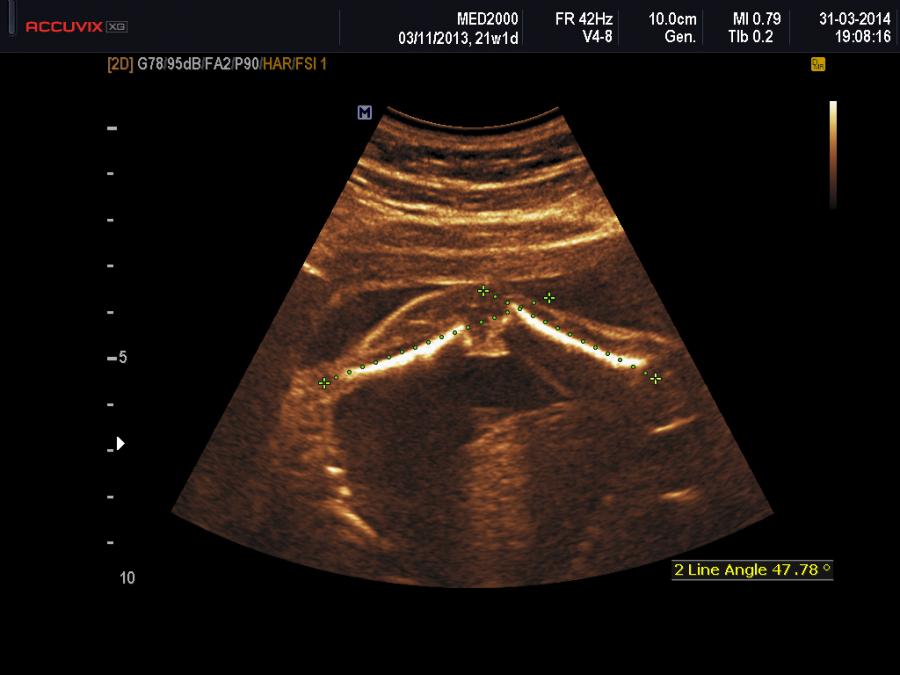

Con l'ecografia è possibile studiare i rapporti articolari tra tibia e femore confrontando le linee tangenti alla diafisi di queste due ossa lunghe. Come si può osservare dallo schema allegato nella sezione Foto, in basso, è possibile documentare l'allineamento o il mancato allineamento di tibia e femore per porre una diagnosi differenziale tra le tre varianti di CGR: iperestensione, sublussazione, dislocazione. Nell'iperestensione le superfici anteriori di tibia e femore sono allineate e le tangenti alle diafisi sono concordanti; nella sublussazione le tangenti alle diafisi di tibia e femore non sono concordanti per cui la tangente alla diafisi della tibia si continua con la superficie anteriore del femore; nella dislocazione le tangenti alle diafisi di tibia e femore non sono concordanti e la superficie posteriore della tibia si allinea con la superficie anteriore del femore.